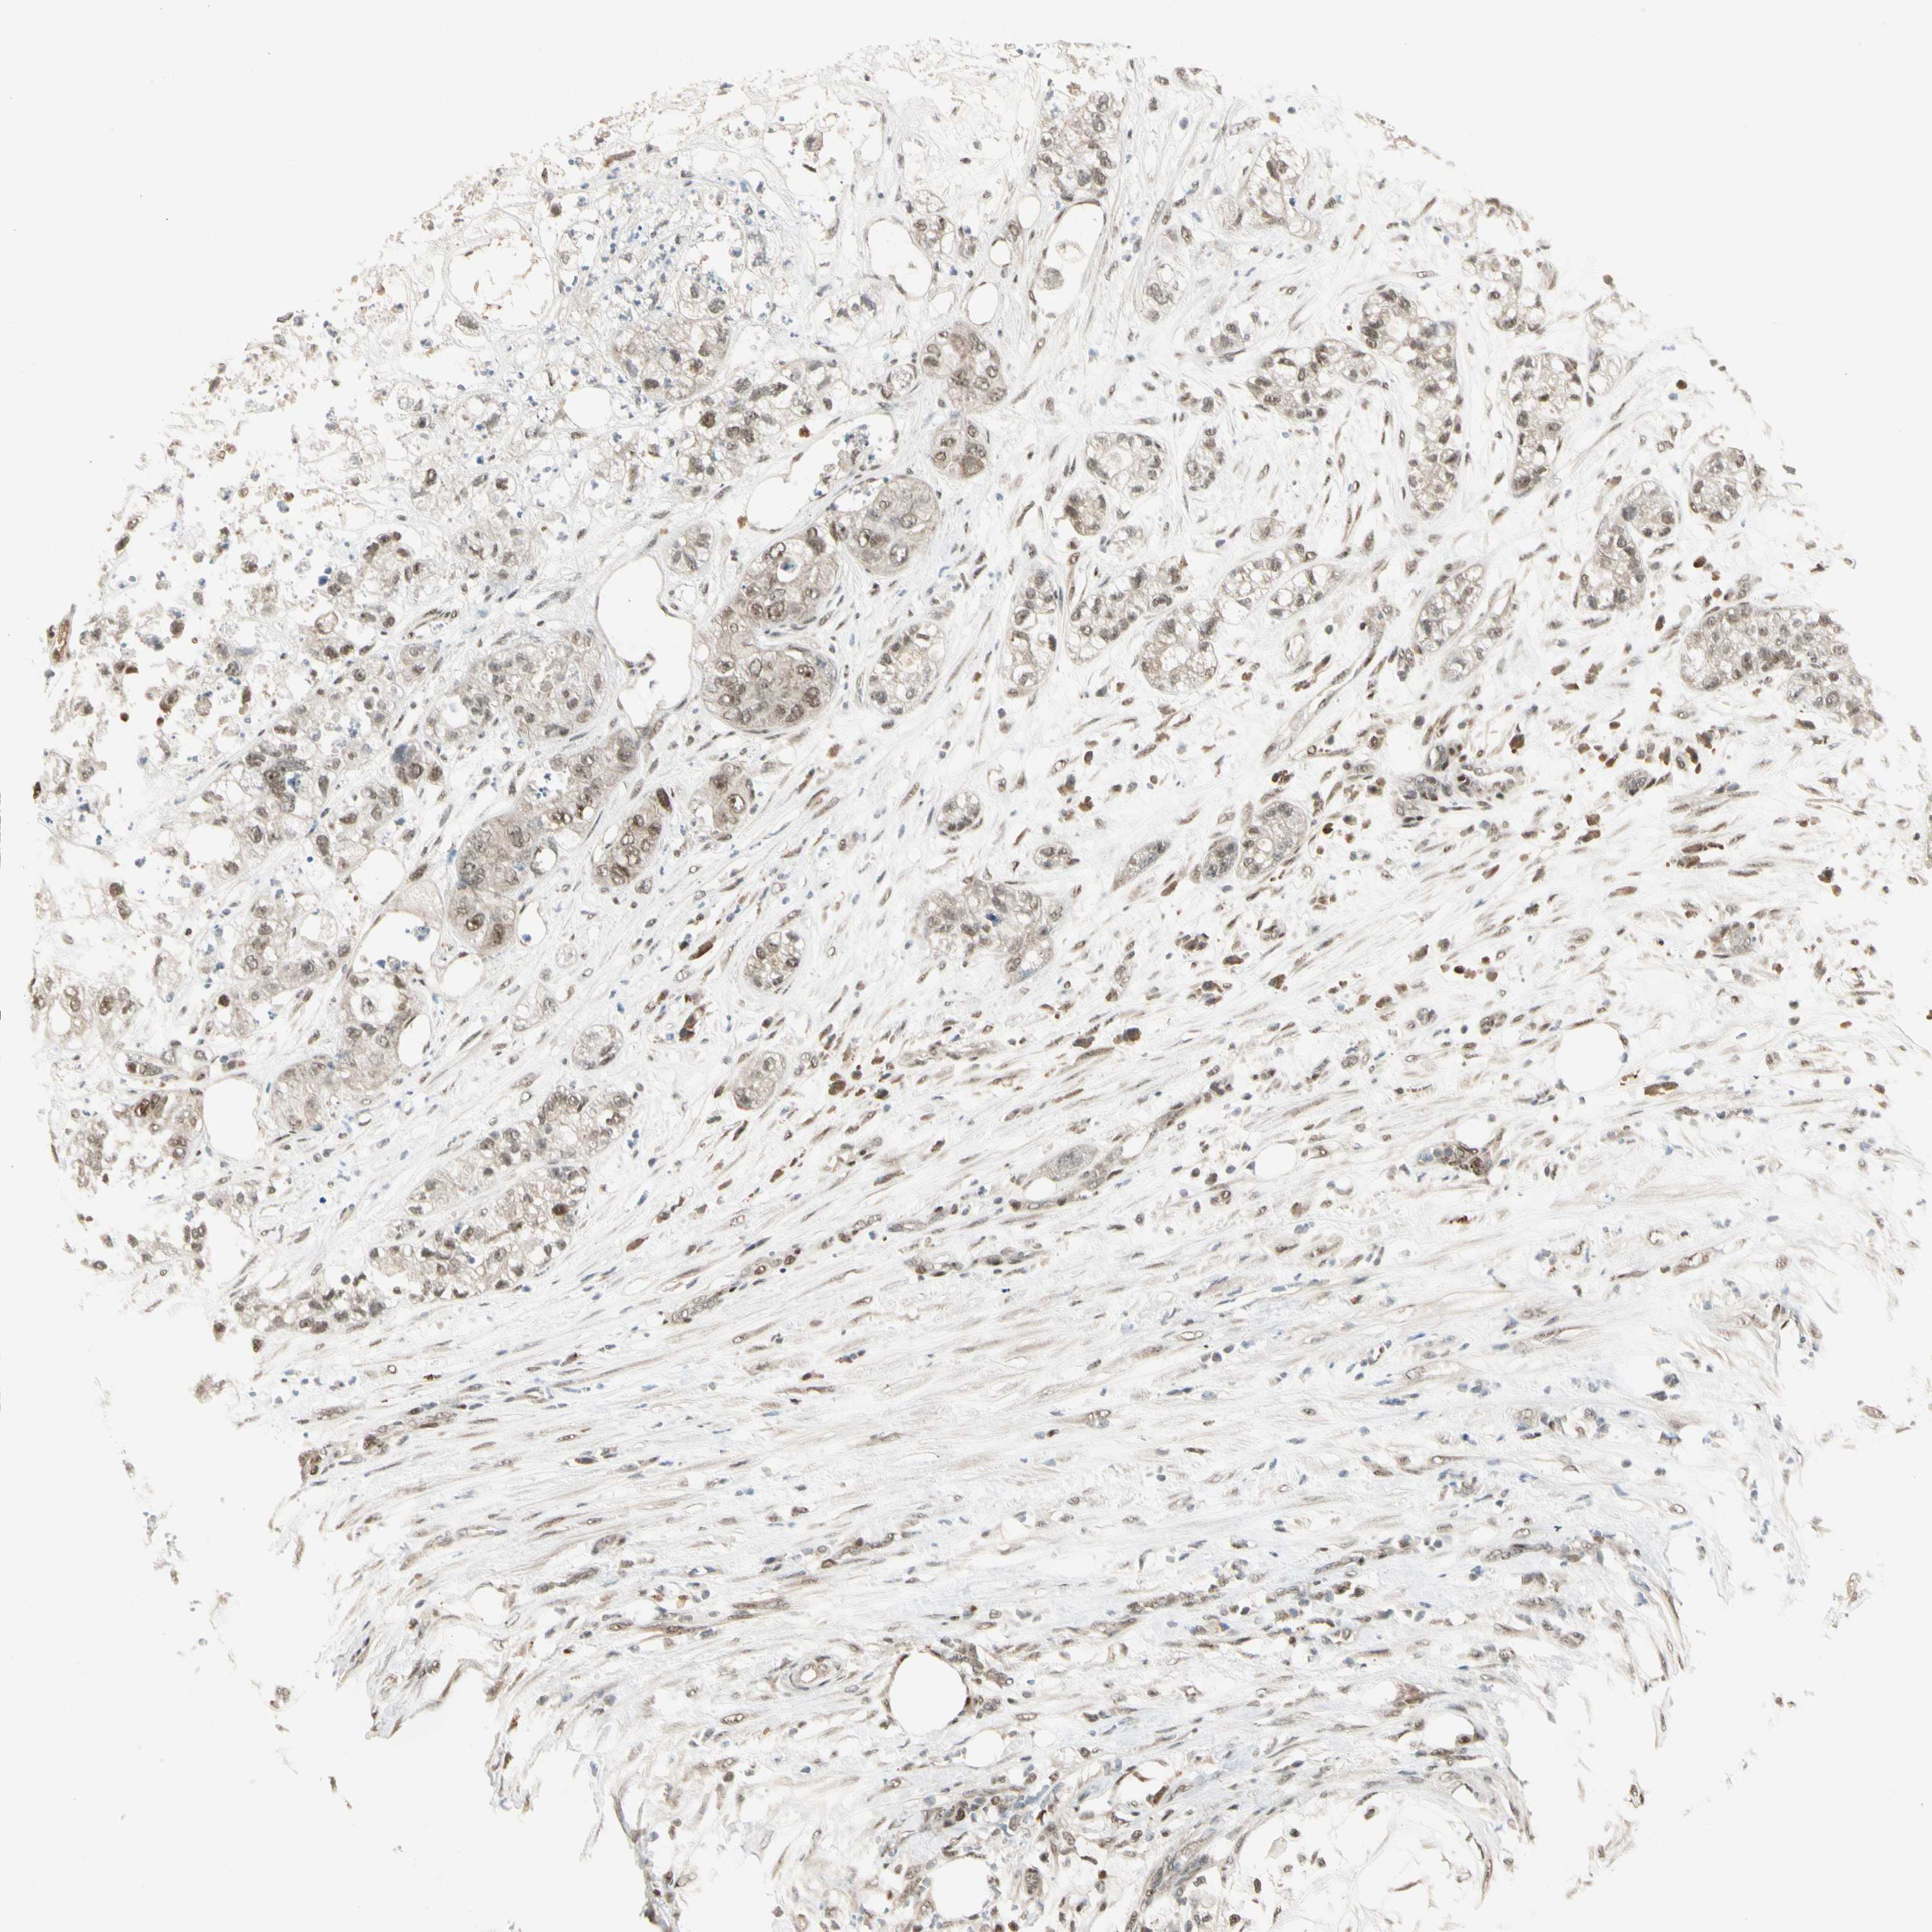

PANCREATIC CANCER - Protein expressioni

A mouse-over function shows sample information and annotation data. Click on an image to view it in a full screen mode. Samples can be filtered based on level of antibody staining by selecting one or several of the following categories: high, medium, low and not detected. The assay and annotation is described here.

Note that samples used for immunohistochemistry by the Human Protein Atlas do not correspond to samples in the TCGA dataset.

Antibody stainingi

Antibody staining in the annotated cell types in the current human tissue is reported as not detected, low, medium, or high, based on conventional immunohistochemistry profiling in selected tissues. This score is based on the combination of the staining intensity and fraction of stained cells.

Each image is clickable and will lead to virtual microscopy that enables deeper exploration of all samples and also displays staining intensity scores, fraction scores and subcellular localization as well as patient and tissue information for each sample.

Antibody HPA007990

Staining

High

Medium

Low

Not detected

Intensity

Strong

Moderate

Weak

Negative

Quantity

>75%

75%-25%

<25%

None

Location

Nuclear

Cytoplasmic/membranous

Cytoplasmic/membranous,nuclear

Adenocarcinoma, NOS